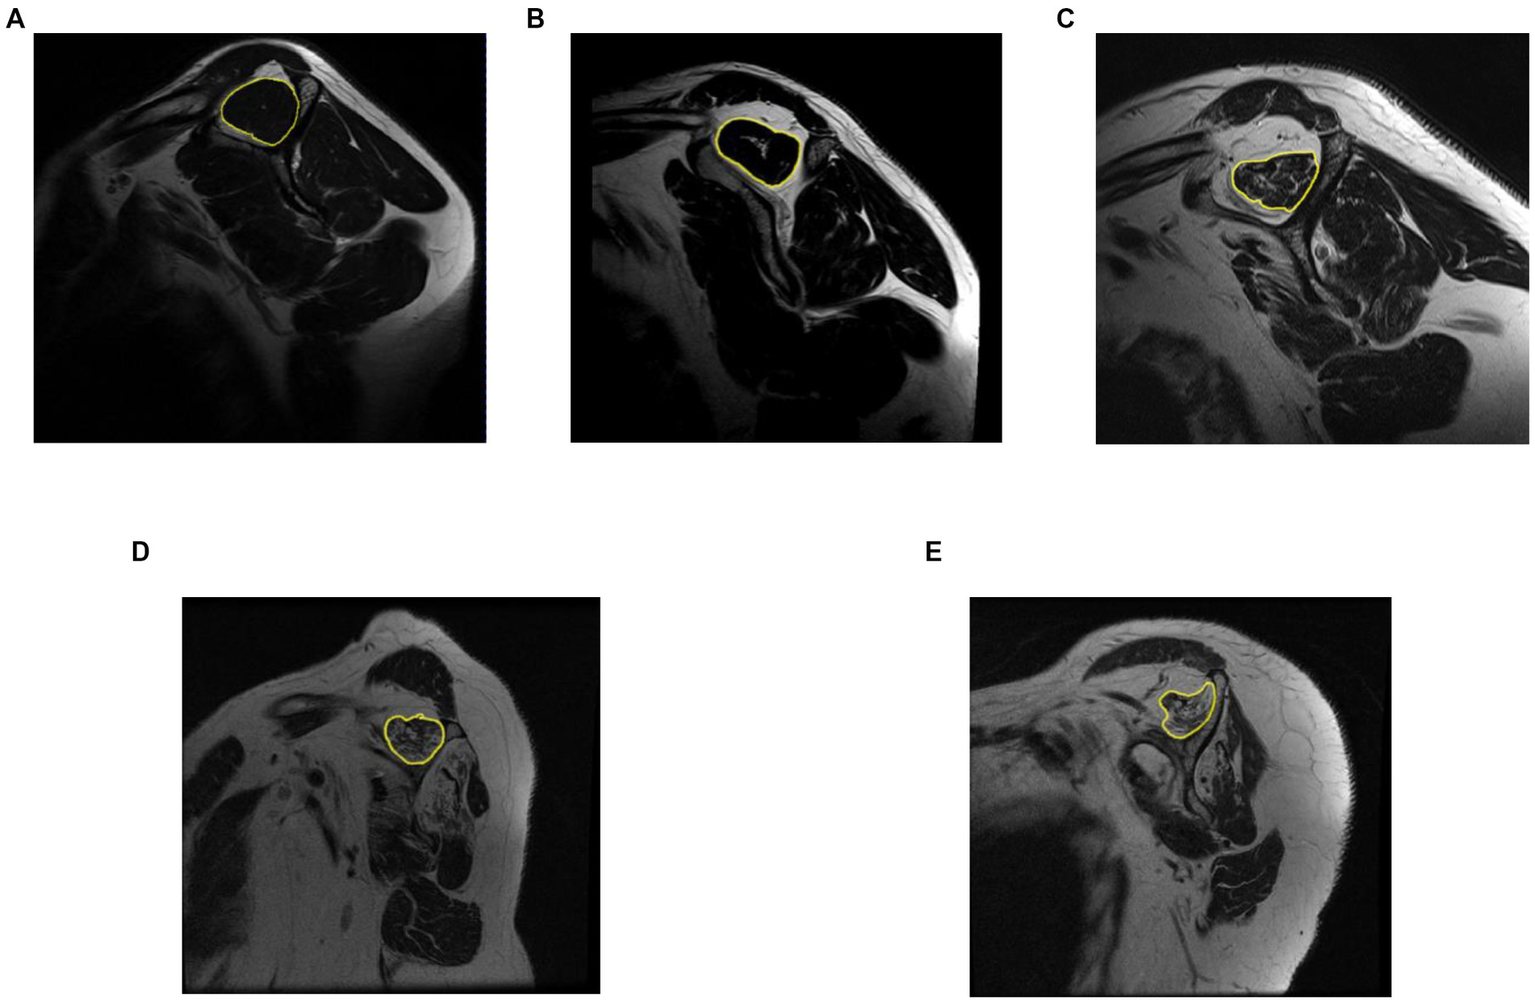

We based our criteria on Goutallier’s fatty infiltration definitions. The original paper proposed five levels of fatty infiltration (zero to four) about the qualitative presence of fat in the muscle. A level of zero means there is no fat in the muscle. As fatty infiltration increases, Goutallier’s scale assigns a greater value. A level four means that there is more fat than muscle present. Figure 5 shows a representative MRI for every Goutallier’s fatty infiltration level.

Figure 5

Representative MRI for each Goutallier’s fatty infiltration scale. Level 0,1, 2, 3, and 4, are shown in sub-image (A–E), respectively.